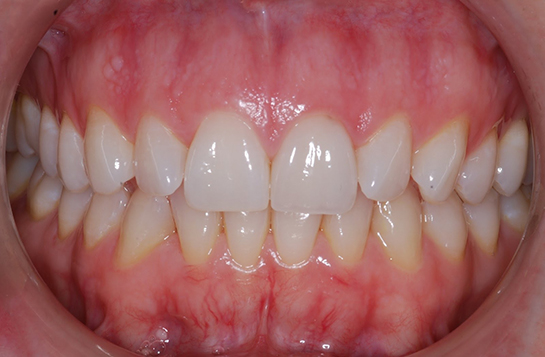

İyileşme Süreci Diş çekimi sonrası iyileşme süreci, bireyden bireye değişiklik göstermekle birlikte genellikle aşağıdaki aşamalardan oluşur: